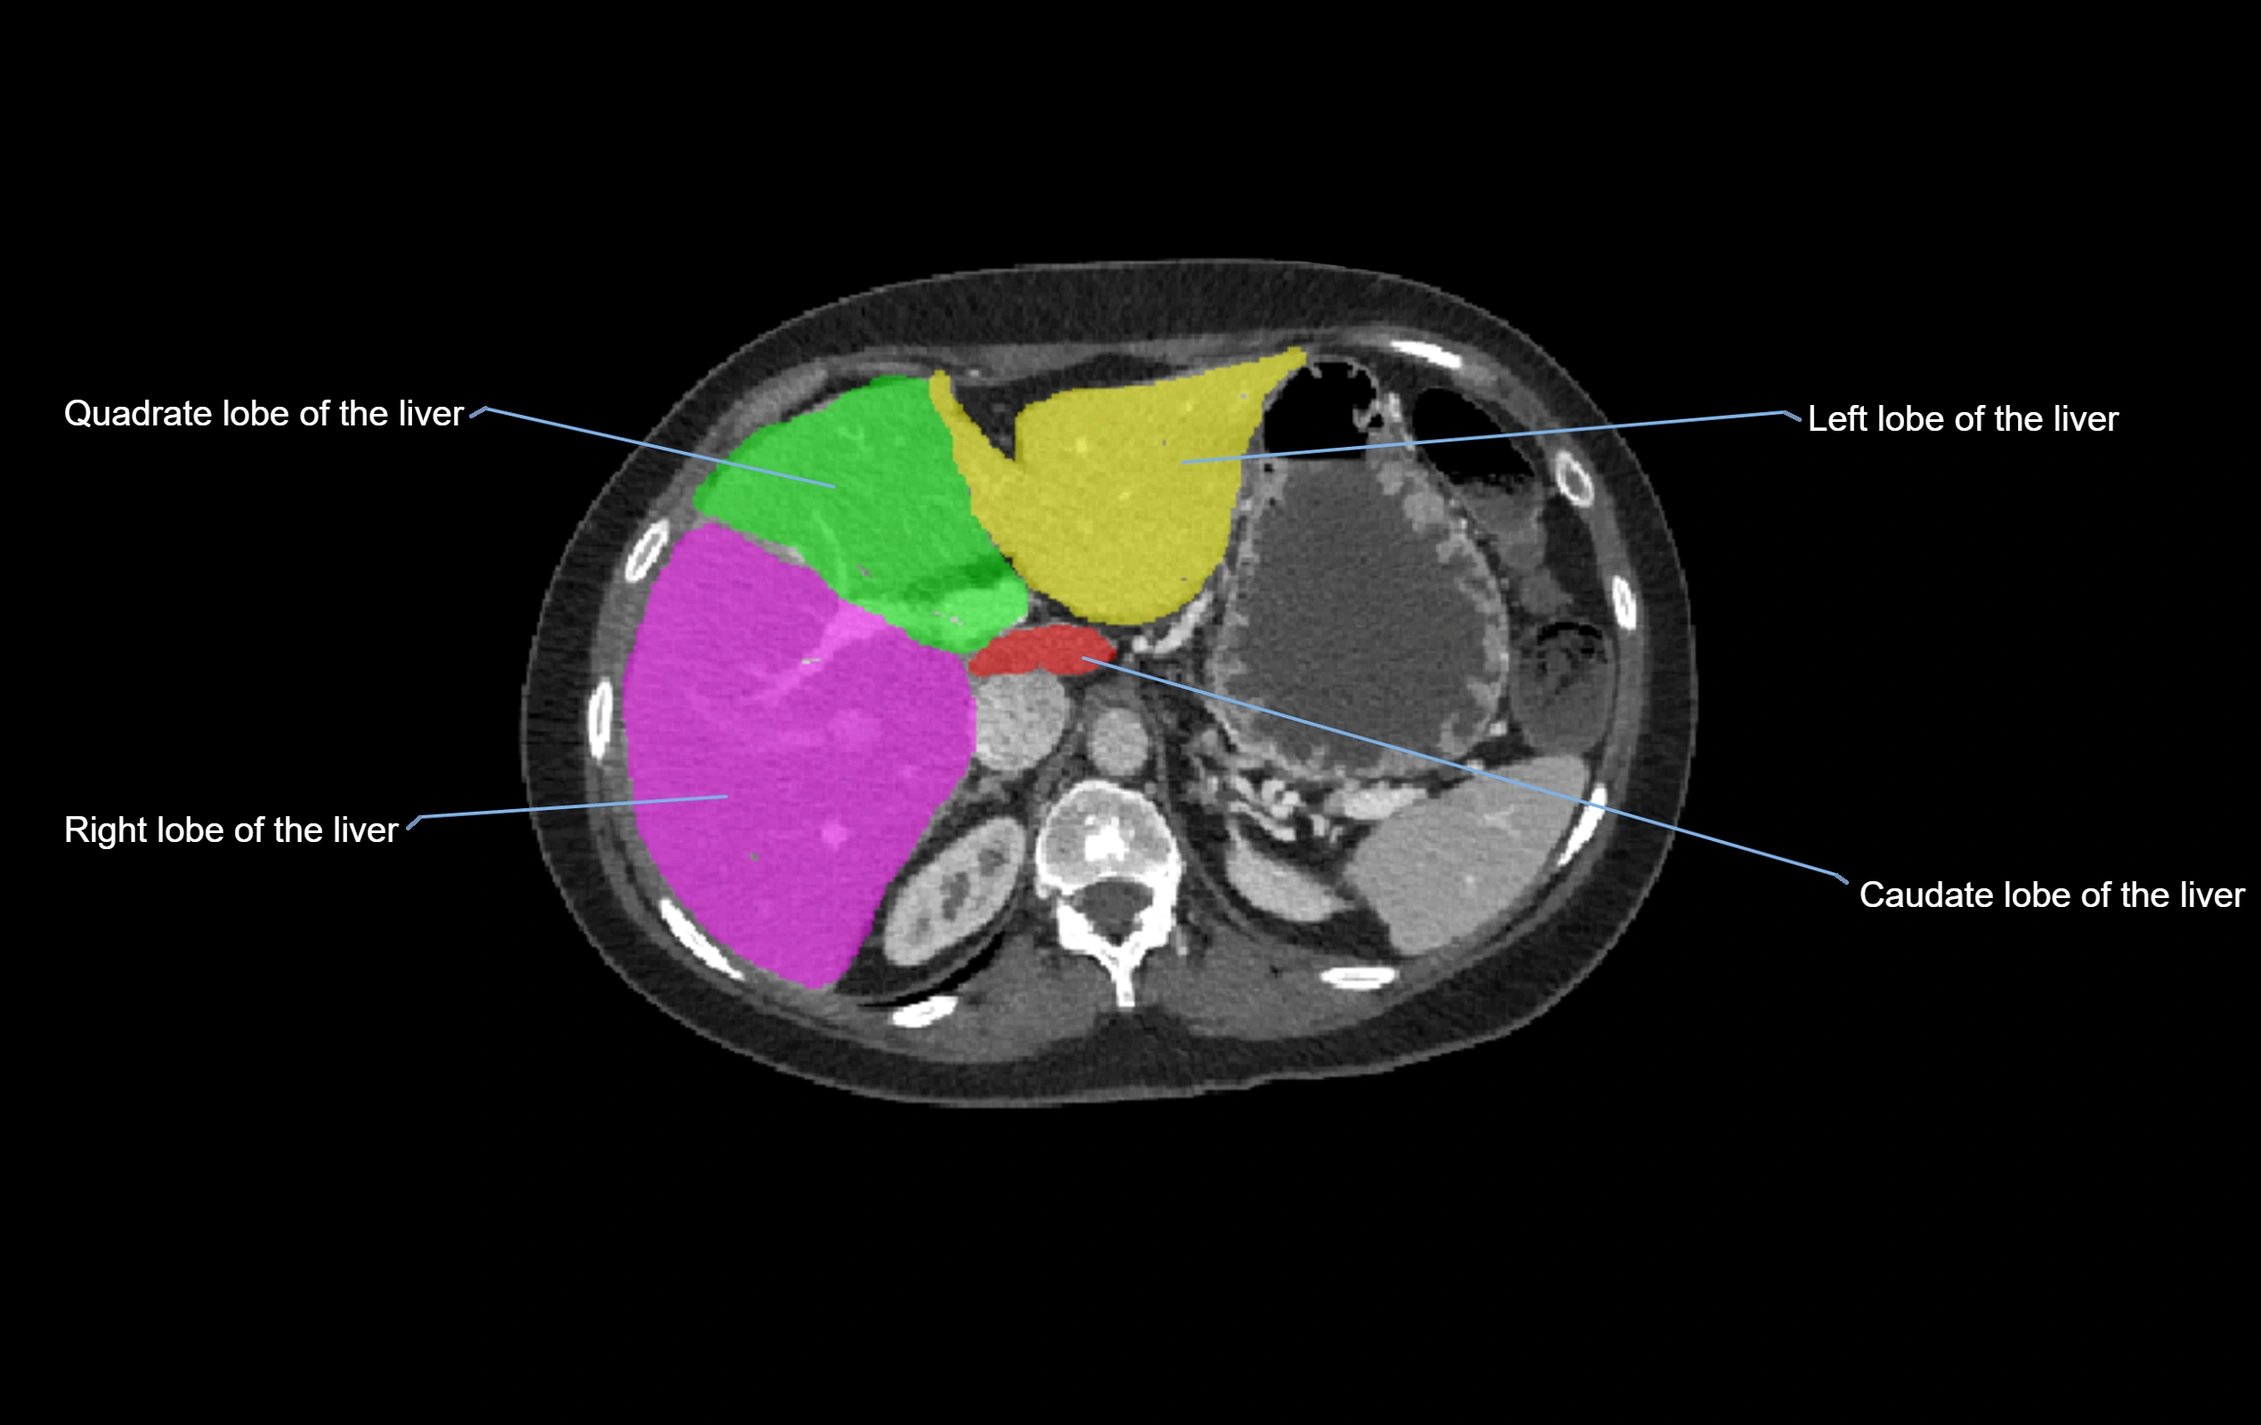

CT Appearance

CT Pre-Contrast:

• Caudate lobe appears as a soft-tissue density, isodense to the rest of the liver

• Enlargement may be appreciated in cirrhosis or Budd–Chiari syndrome

CT Post-Contrast:

• Homogeneous enhancement in the portal venous phase, similar to rest of liver

• Independent venous drainage into the IVC may be visualized

• Lesions follow characteristic CT enhancement patterns (HCC: arterial hyperenhancement with washout; hemangiomas: peripheral nodular enhancement with centripetal fill-in)

CT Venous Phase (functional significance):

• Caudate lobe often enhances relatively more than other lobes in Budd–Chiari syndrome, due to preserved venous outflow

CT Image

image